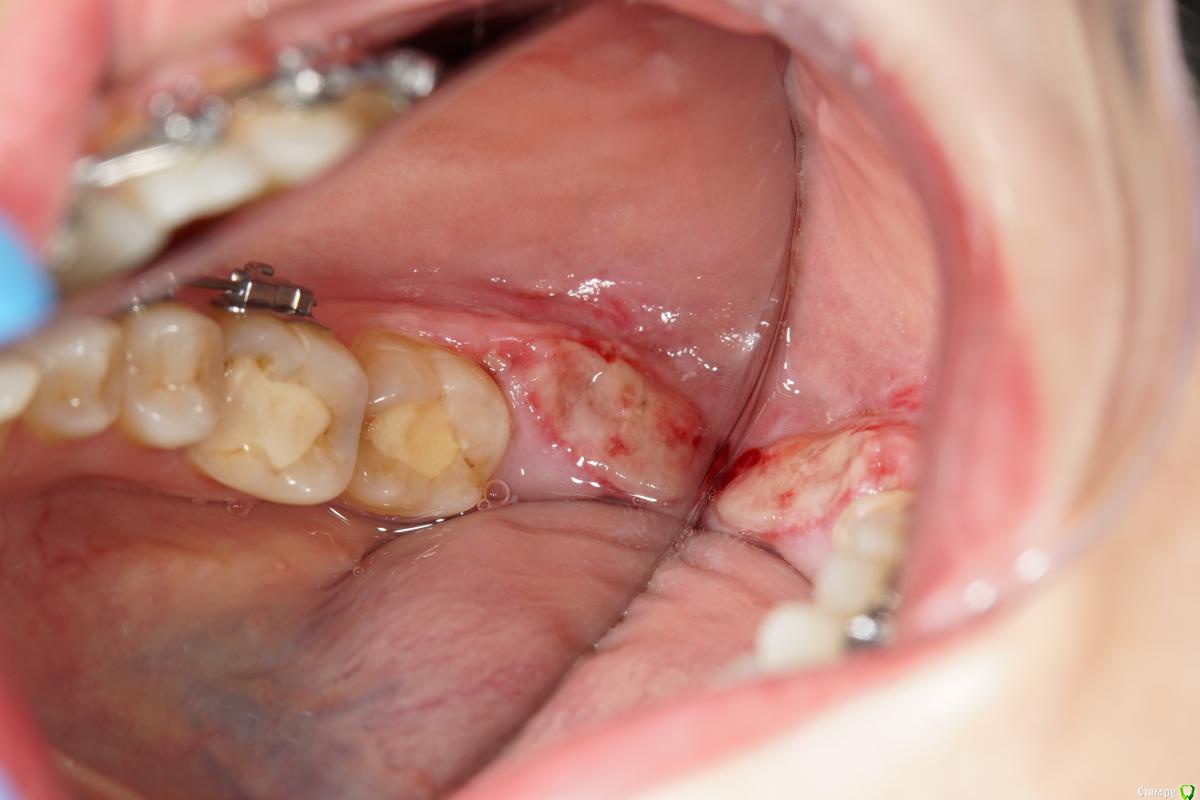

колесников Опубликовано 1 апреля, 2018 Автор Поделиться Опубликовано 1 апреля, 2018 (изменено) Бытует мнение,что капсулу фолликула ретенированой 8ки надо удалять . полностью и тщательно. Аргументов я уже не помню,вроде бы как она стремительно гранулирует,затрудняя регенерацию лунки и кажется что то подобное было у меня в начале практики,что я поверил в эту теорию. Но капсула из этого клин случая ,своей плотностью ,эластичностью и крепостью прикрепления язычно,толкнула меня на эксперимент использовать ее в качестве покровного материала. Протокол был обычный :сепарация и экстракция моляра,графт в лунку (1 г), далее вместо ретромолярно язычного лоскута-капсула фолликула (не фиксировалась,т.к. легла без натяжения) ,края сопоставлены и ушиты. Течение без симптомное. Через неделю: открывание рта не затруднено, слизистая без признаков воспаления. Прогнозируемо щелевидное расхождение краев в первой трети,но при зондировании все плотно и эпителизировано. Как обычно 1 визит,но течение без сопутствующих дискомфортных ощущений. Случай единичный,но результат мне понравился,если будут соответствующие условия- стану использовать Изменено 1 апреля, 2018 пользователем колесников 2 Ссылка на комментарий